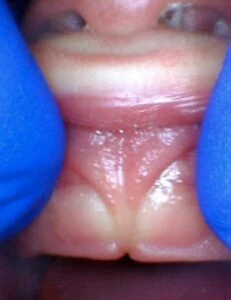

Spectrum of lip restriction in a child

Spectrum of tongue restriction in a child

Posterior tongue-tie in a child seen with lifting the tongue. The posterior or “hidden”tongue-tie can cause the same symptoms including nursing pain and poor weight gain, as a to-the-tip tie in a child